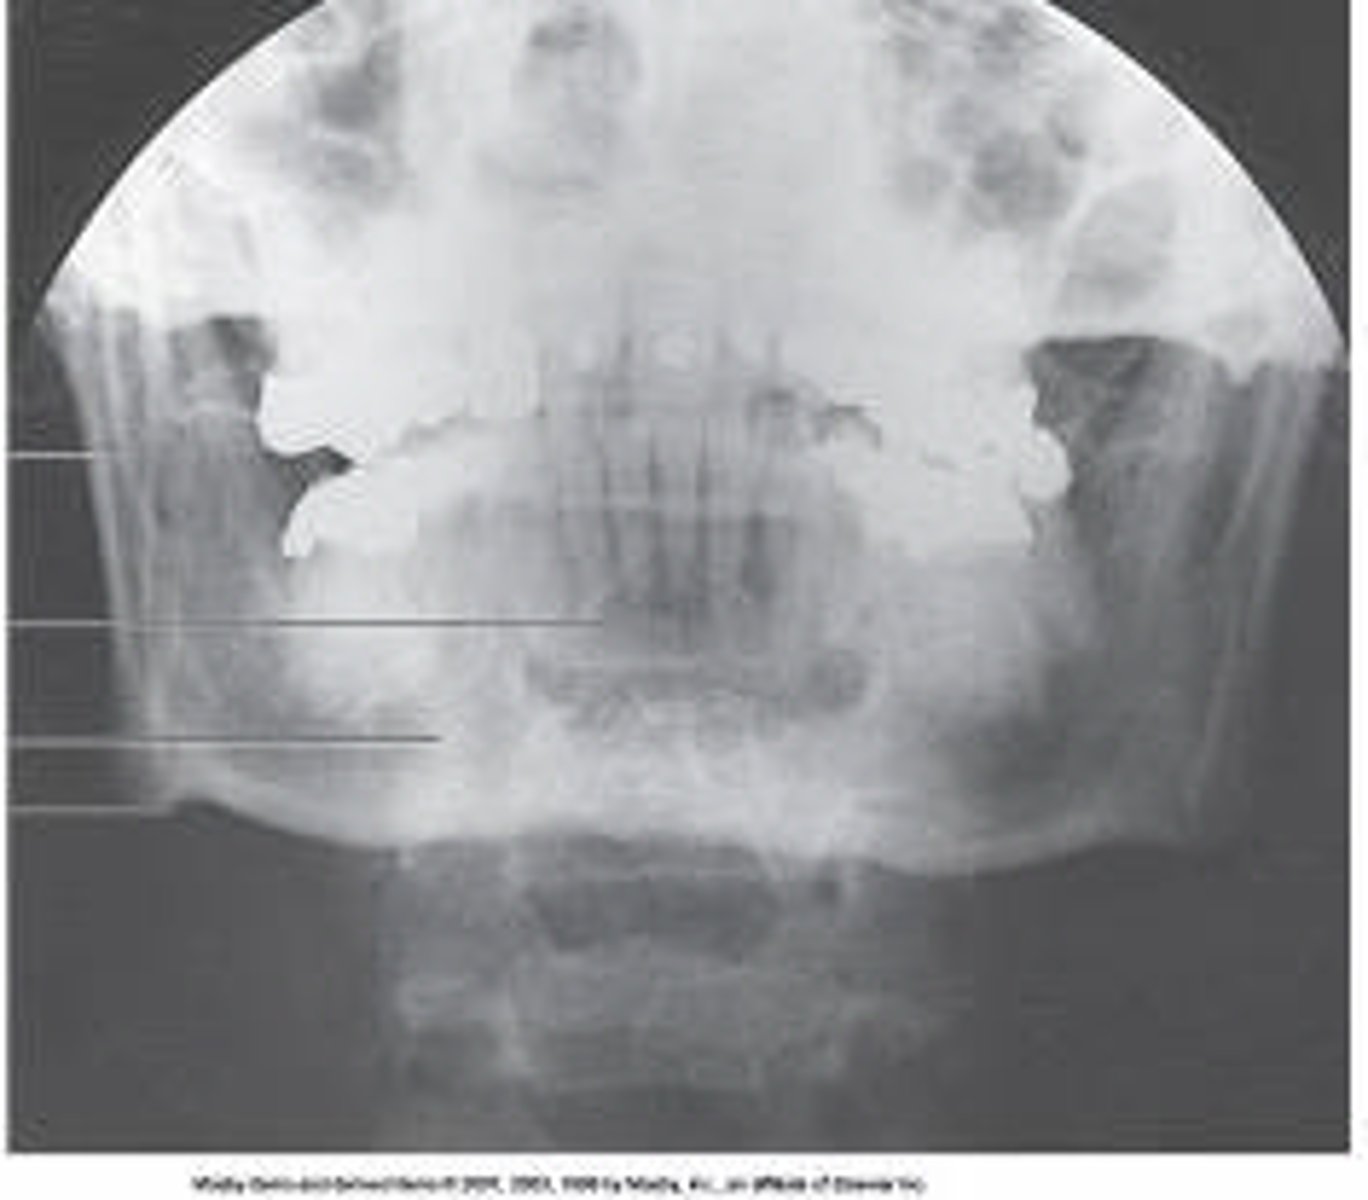

What projection and anatomy is demonstrated in the image below?

SMV of the zygomatic arches

At which level will the central ray be placed for the SMV projection of the zygomatic arches?

At a level 1 inch posterior to the outer canthi

Which of the following lines is placed as nearly parallel to the image receptor as possible for the SMV projection of the zygomatic arches?

IOML